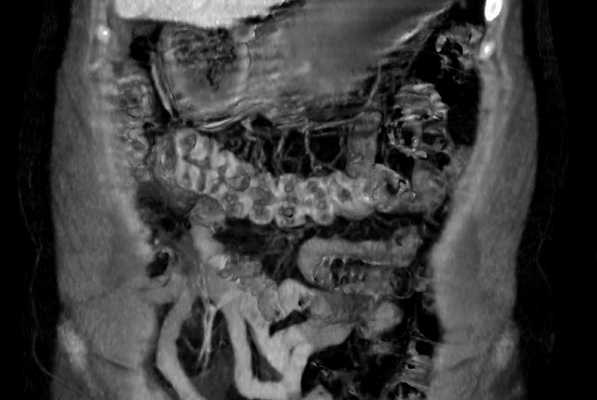

Показания и возможности МРТ в колопроктологии

МРТ, как и другие исследования, основанные на получении изображений срезов (КТ, УЗИ), позволяют получить репродуцируемые изображения в высоком разрешении. Кроме того, МРТ имеет преимущества: качество томограмм не зависит от опыта исследователя, а лучевая нагрузка на пациента отсутствует.

МРТ и КТ в определенной степени взаимозаменяемы, но в некоторых случаях служат дополнением друг другу. Обычно, МРТ имеет преимущества при визуализации мягкотканных структур и зон с различным содержанием воды, например, воспаление и опухоль, мышцы и фасции и т.д.

Повышение контрастности и разрешающей способности в режимах динамического исследования позволяет выполнять неинвазивную реконструкцию и визуализацию сосудов (МРТ ангиография), желчных путей (например, МРТ холангиопанкреатография), оценивать изменения тазового дна в последовательности удержание-натуживание-опорожнение (МРТ дефекография).

б) Показания для МРТ в колопроктологии:

• Стадирование рака: местная распространенность, латеральные границы при раке прямой кишки.

• Динамическая МРТ таза: пролапс органов таза, МРТ дефекография.

• Аноректальные заболевания, МРТ фистулография.